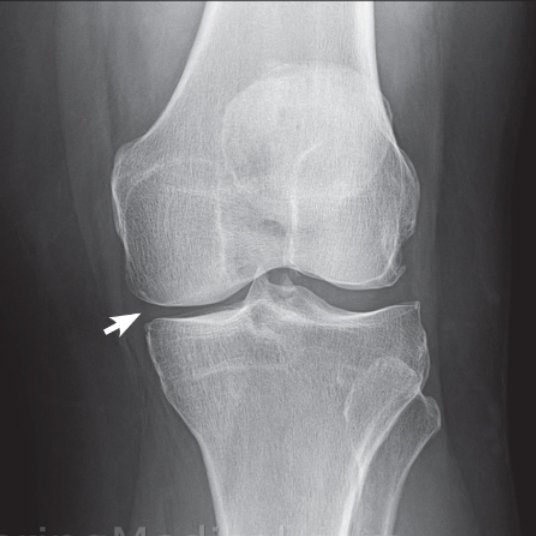

- الخشونة تمر بعدة مراحل.

- كل مرحلة لها علاج يختلف عن المرحلة الاخري.

- المرحلة البسيطة: تكون الآلام بسيطة وغير مؤثرة على حركة المريض.

المرحلة المتوسطة: الآلام تكون متوسطة ومؤثرة على الحركة.

- ظهور انتفخات مع الألم في اوقات متفرقة.

- ظهور نتؤات عظمية في الاشعه